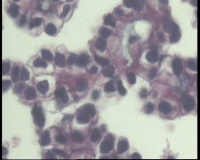

| 一般病史 | 彩超:盆腔可见囊实性回声,囊性为主,大小约5.0x3.7厘米,其内可见分隔回声,部分分隔内回声不纯净,形态欠规整 | ||||

| 标本名称 | 腔镜下右侧卵巢囊肿手术 | ||||

| 大体所见 | 囊壁样组织5.5x5.0厘米,4.5x2.5厘米2块,壁厚0.1-0.2lm,囊壁大部分光滑,局灶见0.7x0.5x0.3厘米淡黄色突起组织,另见淡黄色、肉粉色质软组织2.8厘米一堆。 | ||||